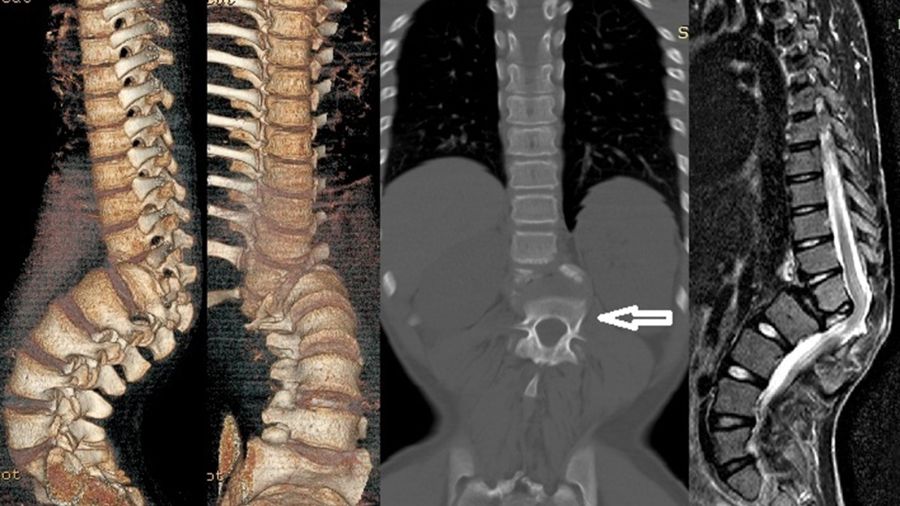

S Rajasekaran—one of the prominent surgeons in the field—has developed useful “spine at risk” criteria for the young spinal-TB patient. If they have facet joint dislocation, retropulsion, lateral translation or toppling, this is likely to develop into post-TB kyphosis, which can result in the tethering of the spinal cord at the apex, leading to myelopathy and paraparesis or paraplegia of the patient at the end. Morbidity levels are high because treatment involves a very extensive surgery from the posterior approach.

Prof Hodgson defined the Hong Kong procedure, which includes anterior radical debridement, removing the necrotic tissues until bleeding healthy bone is observed. This is followed by autogenous grafting with the ribs or iliac bone. The patient is then put into a cast or brace, and the spine generally fuses very well. This technique was used for a very long time and proved really effective. The Medical Research Council, which was a working group involving three centers, took a different approach to spinal TB treatment and then compared their results every 10 years. This provided us with a very well-structured approach based on a treatment flow chart at the end of 20th century.

While the Hong Kong treatment remains the gold standard, modern advances in materials science have allowed us to move away from structural autografts, which can introduce another morbidity. From the late 1990s we have found that bacteria in the spine struggles to attach to titanium, so you can safely use titanium in an infected area after very good debridement. Then, when the abscess and necrotic tissue are removed, you can add a titanium cage without having to use, for example, structural iliac bone.